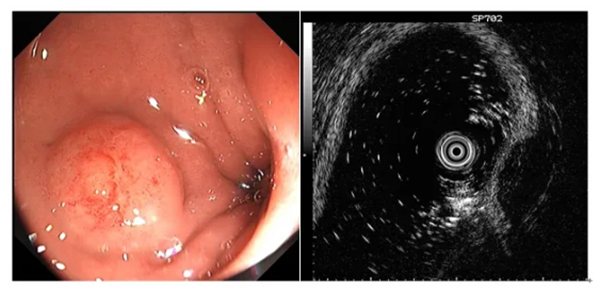

圖示超聲內(nei)鏡判斷(duan)黏膜下腫物(wù)性質(zhi)